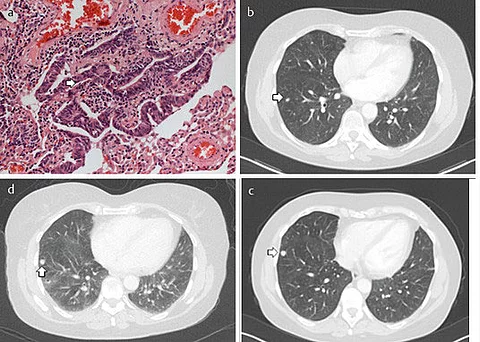

Die 59-jährige Patientin gibt an, zunehmende Atembeschwerden zu haben. Sie weiß von einer Asthma-Erkrankung, die seit vielen Jahren therapiert wird, und ist Nichtraucherin.